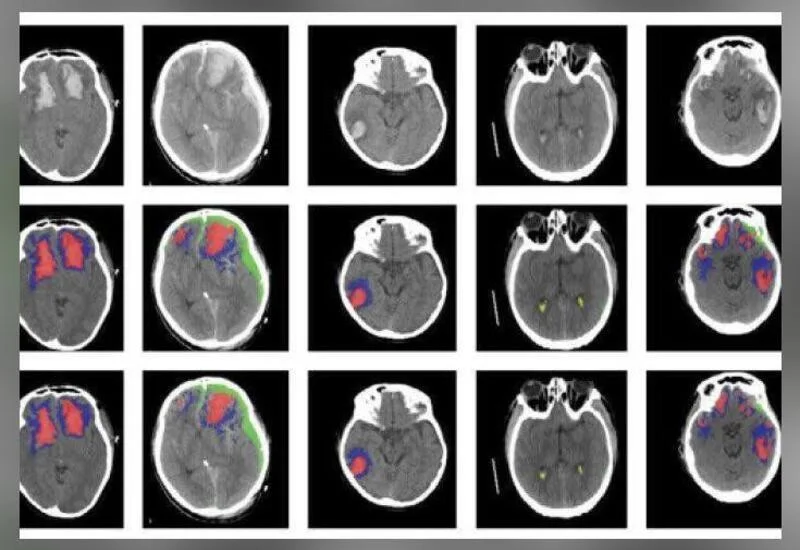

8. AI tool to detect different types of brain injuries developed by researchers

Researchers from the University of Cambridge and Imperial College London have developed an artificial intelligence (AI) algorithm that detects and identifies different types of brain injuries. The researchers have clinically validated and tested the developed model on large sets of CT scans and have found it successful to detect, categorize, quantify, and distinguish different types of the brain injuries. The results, of success, were released in the journal ”The Lancet Digital Health”. This newly developed model could be useful in large-scale research studies, for the development of personalized treatments that suit different kinds of head injuries.